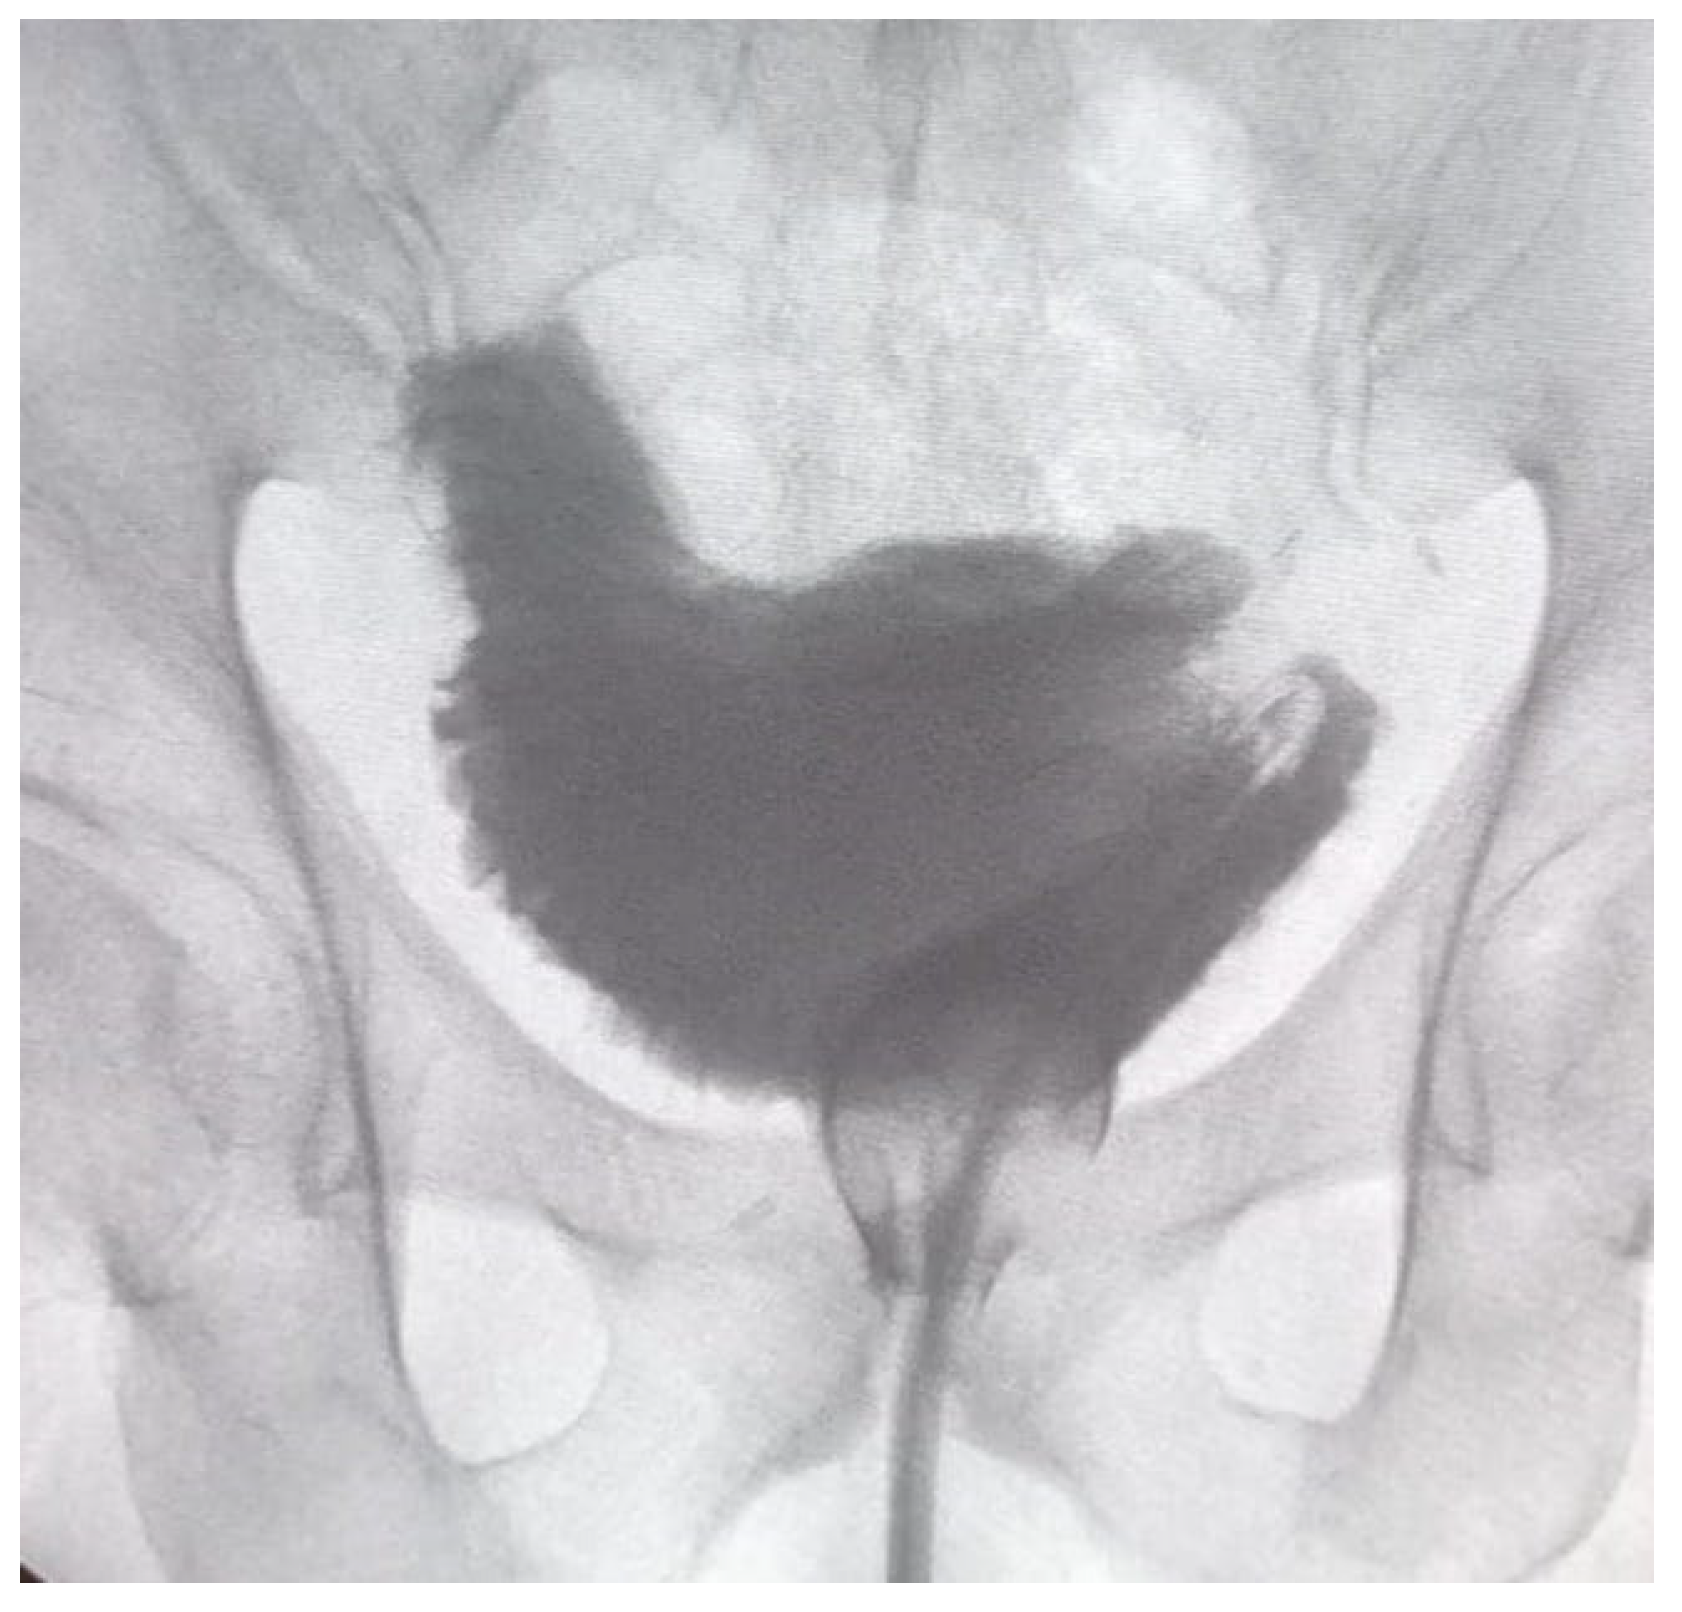

In the case of neobladder reconstruction, the technique we used was that described by Asimakopoulos et al. [9]. A 40–50 cm ileal segment is isolated; the portion with a more adequate mesenteric length is chosen to be brought down to the pelvis. The median part of the isolated ileal segment is pushed towards the urethral stump, and the ileo-urethral approximation represents the first step. A modified posterior reconstruction is performed, with the first layer involving Denonvillier’s fascia and the rhabdosphincter and the second layer approximating the neobladder neck (created with a 1,5 cm ileal incision) and the urethral stump. Afterwards, the anastomosis is carried out; either the posterior reconstruction or ileo-urethral anastomosis is performed with a double-armed barbed suture (Stratafix3–0, Ethicon). The technique proceeds with the isolation of both ileal segments at each side using a mechanical laparoscopic stapler, and ileal-ileal anastomosis is accomplished. The reverse tubular U-segment of the ileum is detubularized to configure the neobladder. The reconstruction starts from the suture of the posterior plane, and then the cranial part is folded downwards toward the bladder neck to create the orthotopic reservoir with two lateral limbs. The neobladder is tested for leakage; uretero-neobladder anastomosis is then performed with direct anastomosis of each spatulated ureter in the dorsal part of the limbs (4–0 monocryl). Ureteral stents are placed before suturing the anterior plate and are brought out through the anterior abdominal wall. Figure 1 represents the cystogram of a neobladder before removing the trans-urethral catheter.

Figure 1.

Orthotopic neobladder at a cystogram performed 18 days after surgery, before removing the urethral catheter.